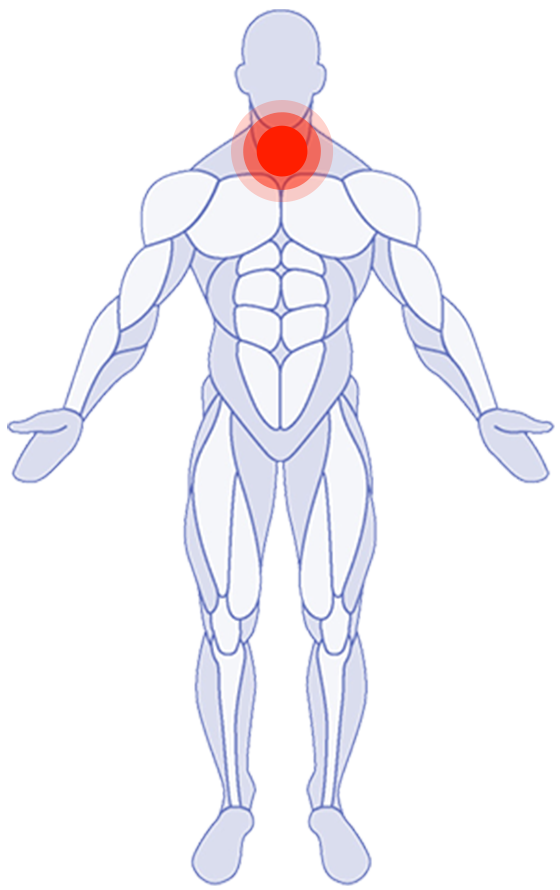

Where do you need attention?